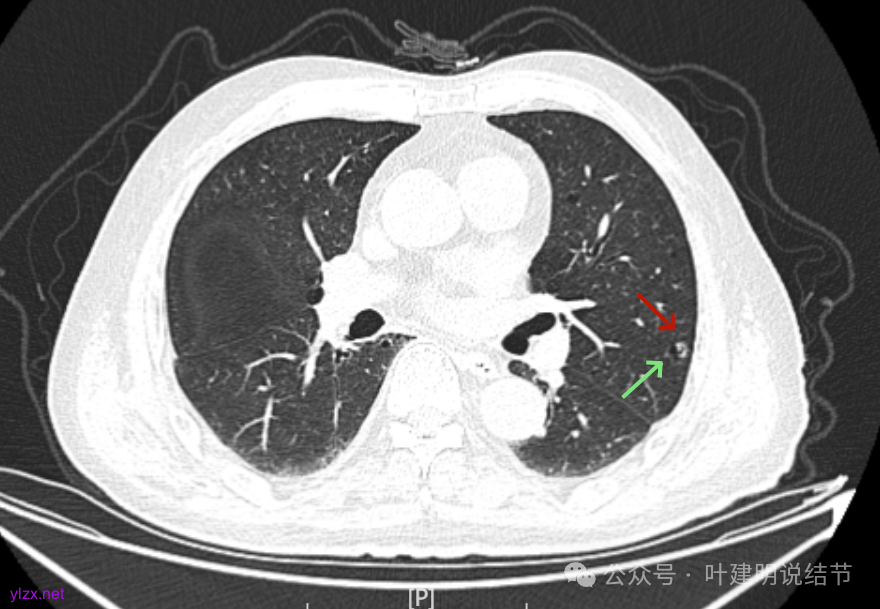

先来看2025年1月的影像:

有囊腔,表面不平,部分囊壁是磨玻璃成分。

病灶囊壁稍不均,多密度较高,表面欠平。

病灶整体的囊壁稍不均,靠内侧有磨玻璃成分。

囊壁不厚但密度较高。

囊腔内壁稍显不光滑,有少许突起于囊腔内。

上图也见囊腔内壁有突起,此层囊壁大部分呈磨玻璃密度。

边缘区是淡磨,内壁少许突起。

左肺上叶红色这处是囊腔型病灶,囊壁略不均,似有微小血管进入囊壁,对比2023年4月整个囊腔来讲有扩大,需要考虑囊腔型肺癌的可能性大。右侧蓝色的并不是典型囊腔型肺癌的表现,再加上两肺绿色这些慢支肺气肿与肺大泡的影像,右侧的就更加不确切,至少近期不能够考虑右侧也要开刀的事情。其实左侧的主病灶相对于其他表现更典型的囊腔型肺癌来说,由于囊壁密度偏高,也不是百分百必定是肺癌。我的想法还是先等脑梗情况稳定,并且间隔4~6个月复查病灶再有进展在考虑单孔胸腔镜下局部切除就可以。淋巴结可以考虑采样,但一般不至于阳性。破是不会切破的。消融不建议,囊腔灶更难通过穿刺获得病理依据,况且东西在边上,能局部楔切,当然首选手术。意见供参考!

左侧这个病灶总体上看仍是囊腔型肺癌可能性大些,但因为其两肺存在多发肺大泡的基础,而且囊壁除了结节状高密度的以外,其他的部分虽欠均匀,但差别并不太大。所以100%恶性还是难以认定的。假如没有脑梗情况,位置在边上,早点切了明确并去除病灶当然是可行的。但在反复脑梗发作的情况下,本身要神经内科情况稳定再手术较为安全,加上无法确切认定必恶性,再适当的随访也不至于影响预后。所以仍是利弊权衡与如何平衡的事情。对于这种囊腔灶,或囊肿为表现的肺癌,其实穿刺不容易阳性,针越过组织的距离并不长,其内又是空的或是液体性质的。从临床经验来看,囊腔型肺癌若囊壁是实性的,确实低分化类型的更常见些,相对风险较高些。但若是囊壁磨玻璃成分的,则也仍是贴壁为主型多见。而且从大小来讲,个人总觉得囊腔部分不能算大小,肿瘤的有形成分应该是减去空腔部分的,所以不能认定CT上测量的包括囊腔部分的来算肿瘤大小的T值。